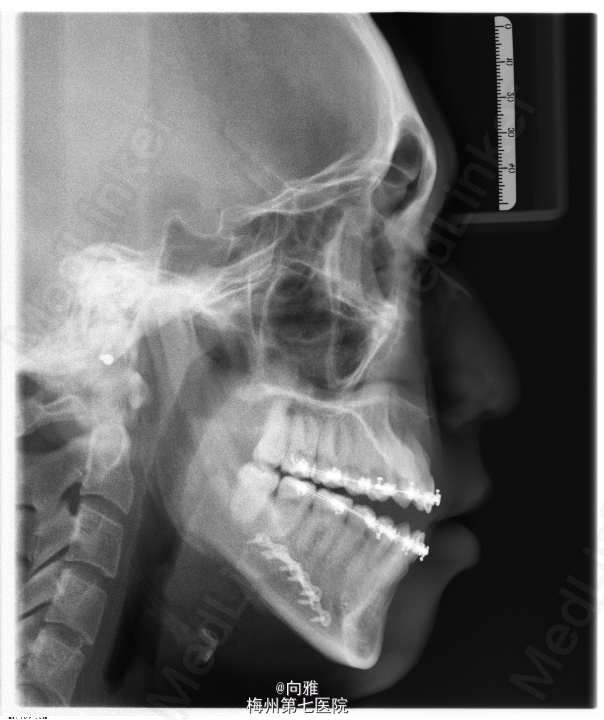

青年男患者,下颌前突十余年,患者于十年余前无明显诱因出现上颌后缩,下颌前突,影响美观及咬合,逐渐加重,未行处理,1年前于我院正畸科就诊,制定“正畸-正颌联合”治疗方案,遂行正畸治疗,现已完善术前正畸,今为行正颌手术入院治疗

1.下颌前突 2.偏颌畸形,全麻下行BSSRO后退术+双侧下颌骨去骨皮质术+坚固内固定术

口内缝线待其自然脱落;继续行颌间弹性牵引,继续至正畸科复诊,术后护理很重要